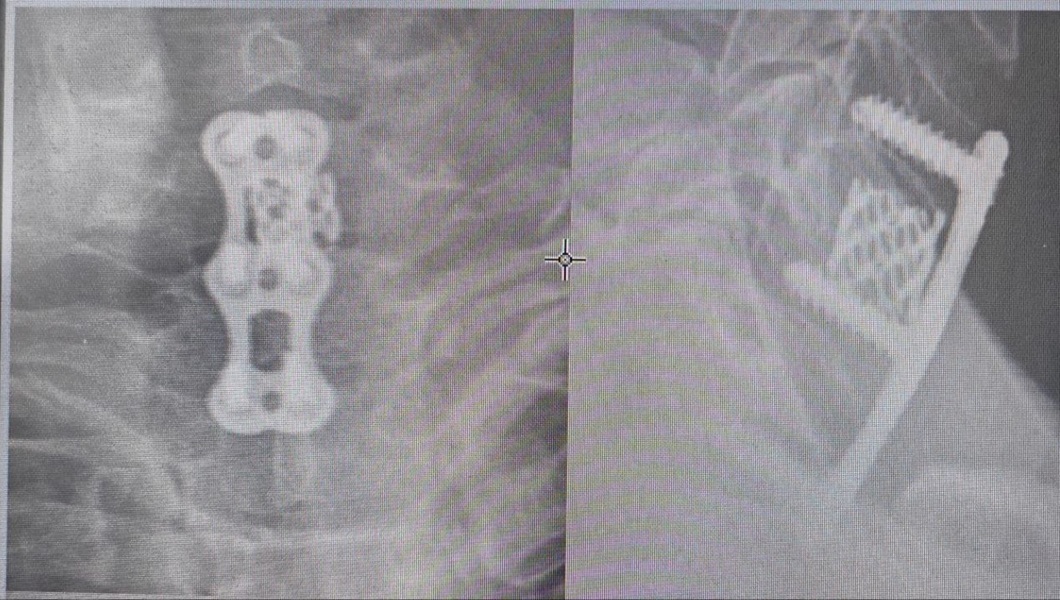

В каждом случае потребовалось оперативное вмешательство — пострадавшим стабилизировали позвоночник при помощи металлоконструкций. В течение недели пациенты находились в травматологическом отделении, затем их выписали на амбулаторное долечивание — подвижность шейного отдела временно будет ограничивать специальный корсет.